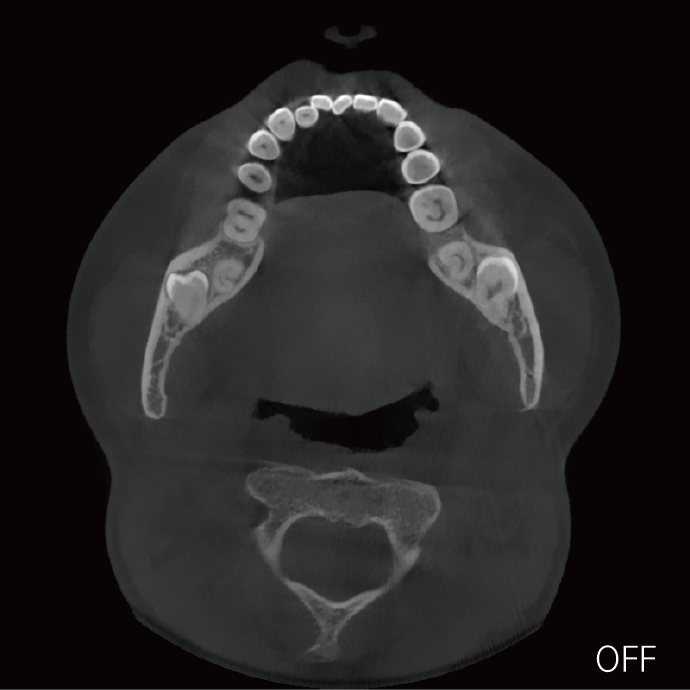

超能去伪 至臻影像

临床样片